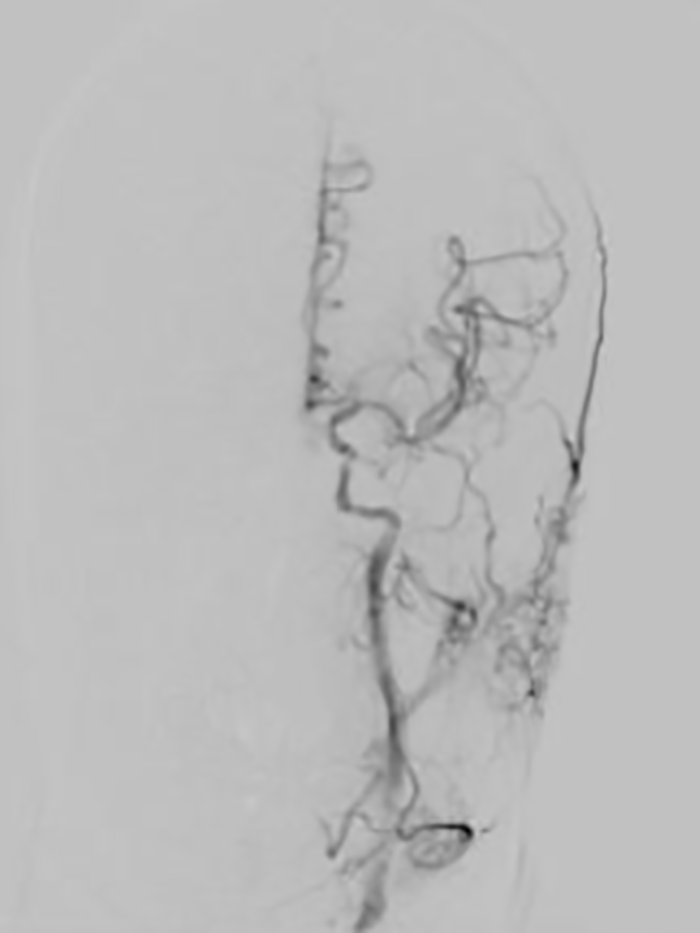

经过两个小时的抢救,患者血管全部再通,手术取得成功!

▲患者术后脑血管完全再通

次日患者神志转清,四肢活动自如,家属见状非常激动,对卒中团队迅速高效的“脑卒中绿色生命通道”以及精准的判断和救治能力竖起了大拇指!